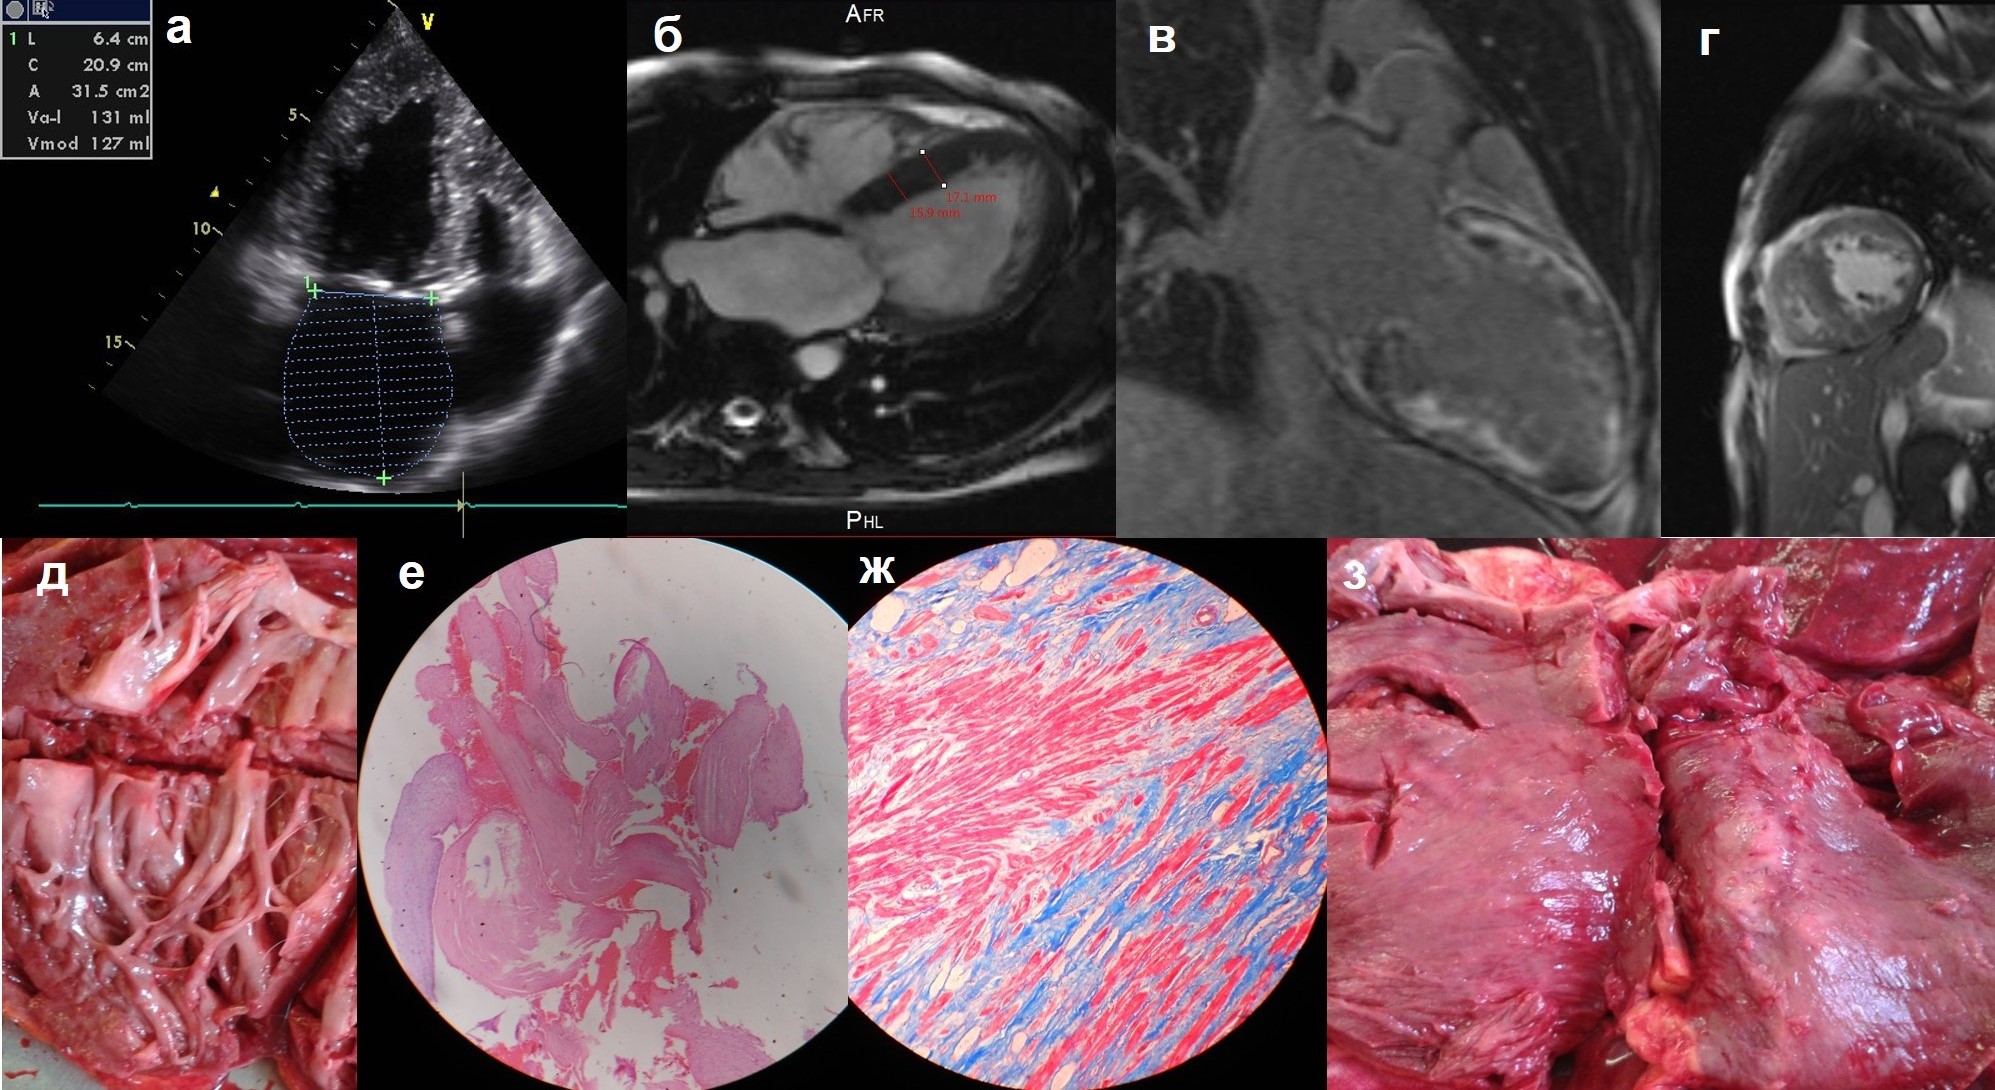

К основным клиническим проявлениям некомпактного миокарда (НКМ) как самостоятельной нозологии относят тромбоэмболический синдром, а также сердечную недостаточность, преимущественно желудочковые нарушения ритма и собственно ишемию, связанные с неполноценным кровоснабжением миокарда под некомпактным слоем. Вместе с тем, встречаются лишь единичные описания инфаркта миокарда (ИМ), в т. ч. “идиопатического”, при НКМ.

Материал и методы. В исследование включено 10 больных — 7 мужчин и 3 женщины, средний возраст — 46,3±15,8 лет, (от 30 до 76 лет) из 85 больных с достоверным диагнозом НКМ, установленным согласно принятым на сегодня визуальным критериям, и развившимся на этом фоне острым ИМ. В 4 случаях наличие НКМ подтверждено с помощью трех визуализирующих методик (ЭхоКГ, МКСТ, МРТ сердца), еще в 4 случаях — с помощью двух. Средний срок наблюдения составил 10,5 [1,75; 32,25] месяцев — от 1 месяца до 1 года. Всем пациентам проведены ЭКГ, суточное мониторирование ЭКГ по Холтеру, ЭхоКГ, определение уровня антител к различным антигенам сердца, ПЦР на ДНК парвовируса В19 и вирусов герпетической группы в крови, 7 коронарографий, 7 МСКТ сердца, определение уровня тропонина (n=7), морфологическое исследование сердца с ПЦР-диагностикой вирусной инфекции (n=6), МРТ (n=5) и сцинтиграфия миокарда с 99mТс (n=6).

Результаты. У 4 из 10 пациентов развитие ИМ стало первым проявлением НКМ. Частота коронарного атеросклероза у больных с ИМ на фоне НКМ составила 20%, однако в большинстве случаев развитие ИМ не связано с наличием коронарного атеросклероза. Внутрисердечный тромбоз верифицирован у 60% больных с ИМ, эмболии в другие органы развились у 30%. Выделены следующие механизмы ИМ: 1) тромбоэмболия в коронарные артерии при наличии тромбов в левых камерах сердца (как в предсердии, так и в желудочке), верифицирована у 1 больной при аутопсии, предполагается еще у пятерых; 2) присоединение миокардита, в т. ч. вирусного, с развитием микроваскулита, тромбозов интрамиокардиальных артерий и очагового некроза в ишемизированном миокарде (n=6); 3) тромбоз коронарных артерий при наличии гемодинамически значимого атеросклероза (вероятно, 1 больной); 4) резкое ухудшение кровоснабжения под некомпактным слоем в условиях малого сердечного выброса, вызванное другими причинами.

Заключение. ИМ является типичным и нередким осложнением НКМ: его частота составила 11,8% в отдельном регистре из 85 больных с синдромом НКМ. Четыре основных механизма ИМ (некроза) при НКМ (эмболия, тромбоз, миокардит, нарушение микроциркуляции) могут сочетаться друг с другом. Развитие ИМ приводит к резкому усугублению исходной систолической дисфункции и желудочковых нарушений ритма: смертность среди больных с ИМ на фоне НКМ составила 20% при среднем сроке наблюдения 10,5 месяцев. В качестве средств по профилактике ИМ при НКМ должны рассматриваться назначение антикоагулянтов как минимум при мерцательной аритмии и систолической дисфункции, своевременная диагностика и лечение миокардита.